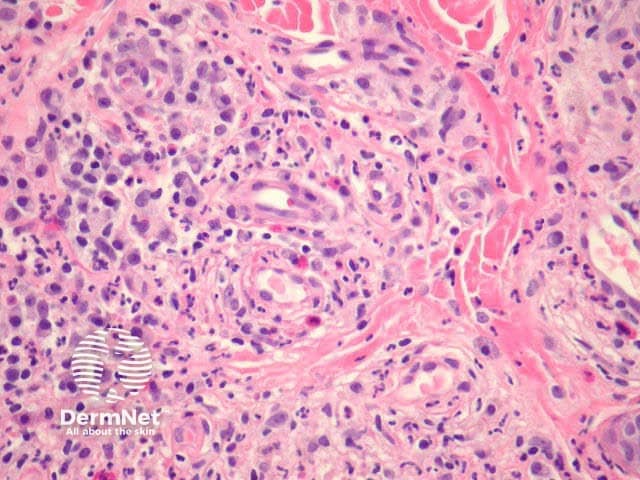

In erythema elevatum diutinum, there is sparing of the papillary and periadnexal dermis (Figures 1, 2). Vascular infiltration in the upper and mid-dermis with predominant neutrophils and fewer lymphocytes, eosinophils and plasma cells (Figures 3, 4, 5). Leucocytoclasia is commonly seen in fresh lesions (Figure 5). Later lesions develop sclerosis with plasma cells and residual foci of leukocytoclastic vasculitis. Sclerosis may be striking and have a storiform pattern (Figures 1, 4).

Figure 5